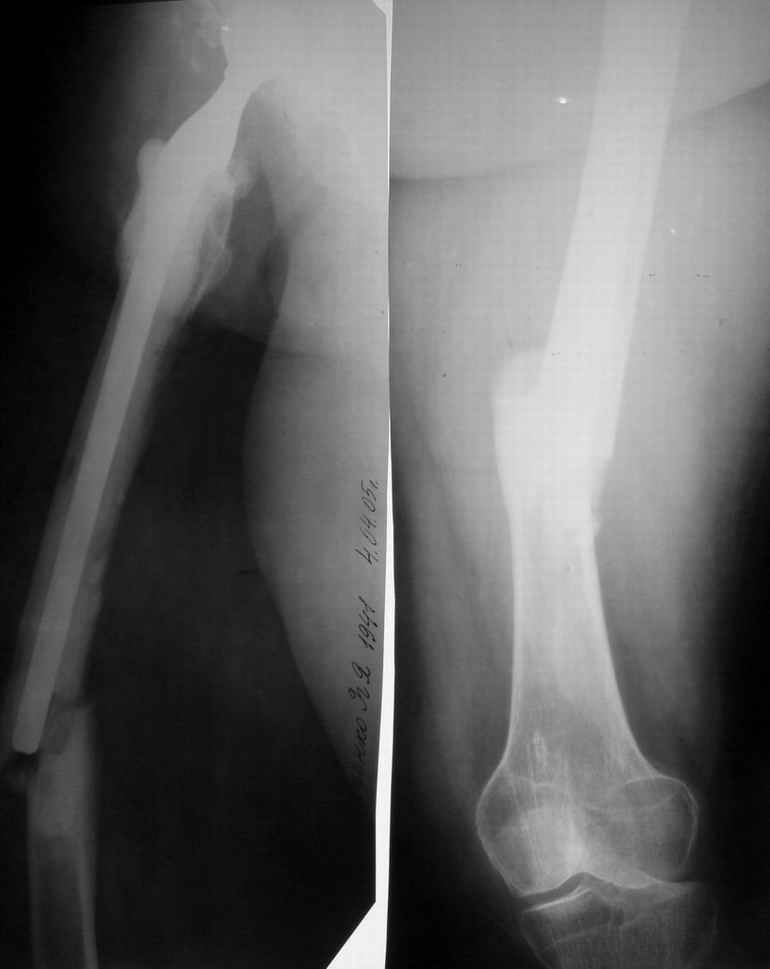

Уважаемые коллеги!Просим доброго совета.Больная 64 лет оперирована в клинике год назад по поводу диспластического коксартроза III ст. Выполнено эндопротезирование левого тазобедренного сустава цементным протезом "Beznoska". В течение месяца после операции дважды - вывих эндопротеза, в связи с чем 17.05.04 пошли на удаление ножки "Beznoska" и установку ревизионной ножки "De Puy".

Послеоперационный период протекал без осложнений. В течение года пациентка полностью реабилитировалась, вернулась к труду (преподаватель).4.04.05 в результате падения на улице получила околопротезный перелом бедра (рентгенограммы прилагаются). Просим Ваших советов относительно дальнейшей тактики лечения пациентки.